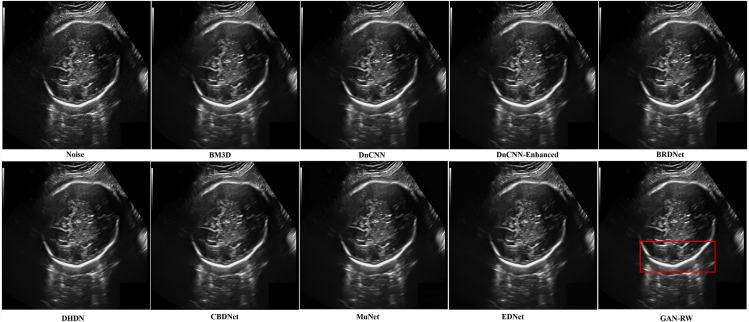

We split the experiments into two parts. First, experiments were performed on Berkeley segmentation (BSD68) datasets corrupted by a simulated speckle. Compared with the eight existing denoising algorithms, the GAN-RW achieved the most advanced despeckling performance in terms of the peak signal-to-noise ratio (PSNR), structural similarity (SSIM), and subjective visual effect. When the noise level was 15, the average value of the GAN-RW increased by approximately 3.58% and 1.23% for PSNR and SSIM, respectively. When the noise level was 25, the average value of the GAN-RW increased by approximately 3.08% and 1.84% for PSNR and SSIM, respectively. When the noise level was 50, the average value of the GAN-RW increased by approximately 1.32% and 1.98% for PSNR and SSIM, respectively. Secondly, experiments were performed on the ultrasound images of lymph nodes, the foetal head, and the brachial plexus. The proposed method shows higher subjective visual effect when verifying on the ultrasound images. In the end, through statistical analysis, the GAN-RW achieved the highest mean rank in the Friedman test.

结果

我们将实验分为两部分。首先,在由模拟散斑损坏的伯克利分割(BSD68)数据集上进行实验。与现有的八种去噪算法相比,GAN-RW在峰值信噪比(PSNR)、结构相似性(SSIM)和主观视觉效果方面实现了最先进的去斑性能。当噪声水平为15时,GAN-RW的PSNR和SSIM平均值分别提高了约3.58%和1.23%。当噪声水平为25时,GAN-RW的PSNR和SSIM平均值分别提高了约3.08%和1.84%。当噪声水平为50时,GAN-RW的PSNR和SSIM平均值分别提高了约1.32%和1.98%。其次,在淋巴结、胎儿头部和臂丛神经的超声图像上进行实验。所提出的方法在超声图像验证时显示出更高的主观视觉效果。最后,通过统计分析,GAN-RW在弗里德曼检验中获得了最高的平均排名。